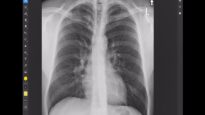

What is a Tension Pneumothorax? | Lecturio Emergency Medicine Mediube Subscribe Subscribed 3 1173 videos 0% 29 Views 0 Likes 2024-04-18 Pulmonology By Mediube 0 Comments (بازدید 29 بار, بازدیدهای امروز 1 ) Show more PREV Pneumothorax for Nursing(collapsed lung) Animation, Treatment, Decompression, Pathophysiology Mediube 2024-04-16 NEXT Tension Pneumothorax Emergency Medicine | Lecturio Mediube 2024-04-18 You might be interested in 0 Anatomy and physiology of the respiratory system Mediube 2024-09-18 0 An introduction to chest CT scanning – anatomy and approach Mediube 2024-01-31 0 What Is Severe Asthma؟ Mediube 2024-05-25 0 Lung Anatomy Mediube 2024-09-22 0 CDC Tuberculosis (TB) Transmission and Pathogenesis Mediube 2024-10-02 0 How to auscultate lung sounds Mediube 2024-01-31 0 Pneumothorax vs Lung Collapse Mediube 2024-04-15 0 What Happens During a CT Lung Scan Mediube 2024-06-06 0 Thoracentesis Mediube 2024-04-27 0 Lung Transplant Patient Journey Mediube 2024-10-02 0 Tuberculosis – causes, symptoms, diagnosis, treatment, pathology Mediube 2024-10-12 0 How to identify normal lung anatomy on chest CT Mediube 2024-06-06 LEAVE YOUR COMMENT Cancel replyYour email address will not be published. Required fields are marked * Save my name, email, and website in this browser for the next time I comment. Δ